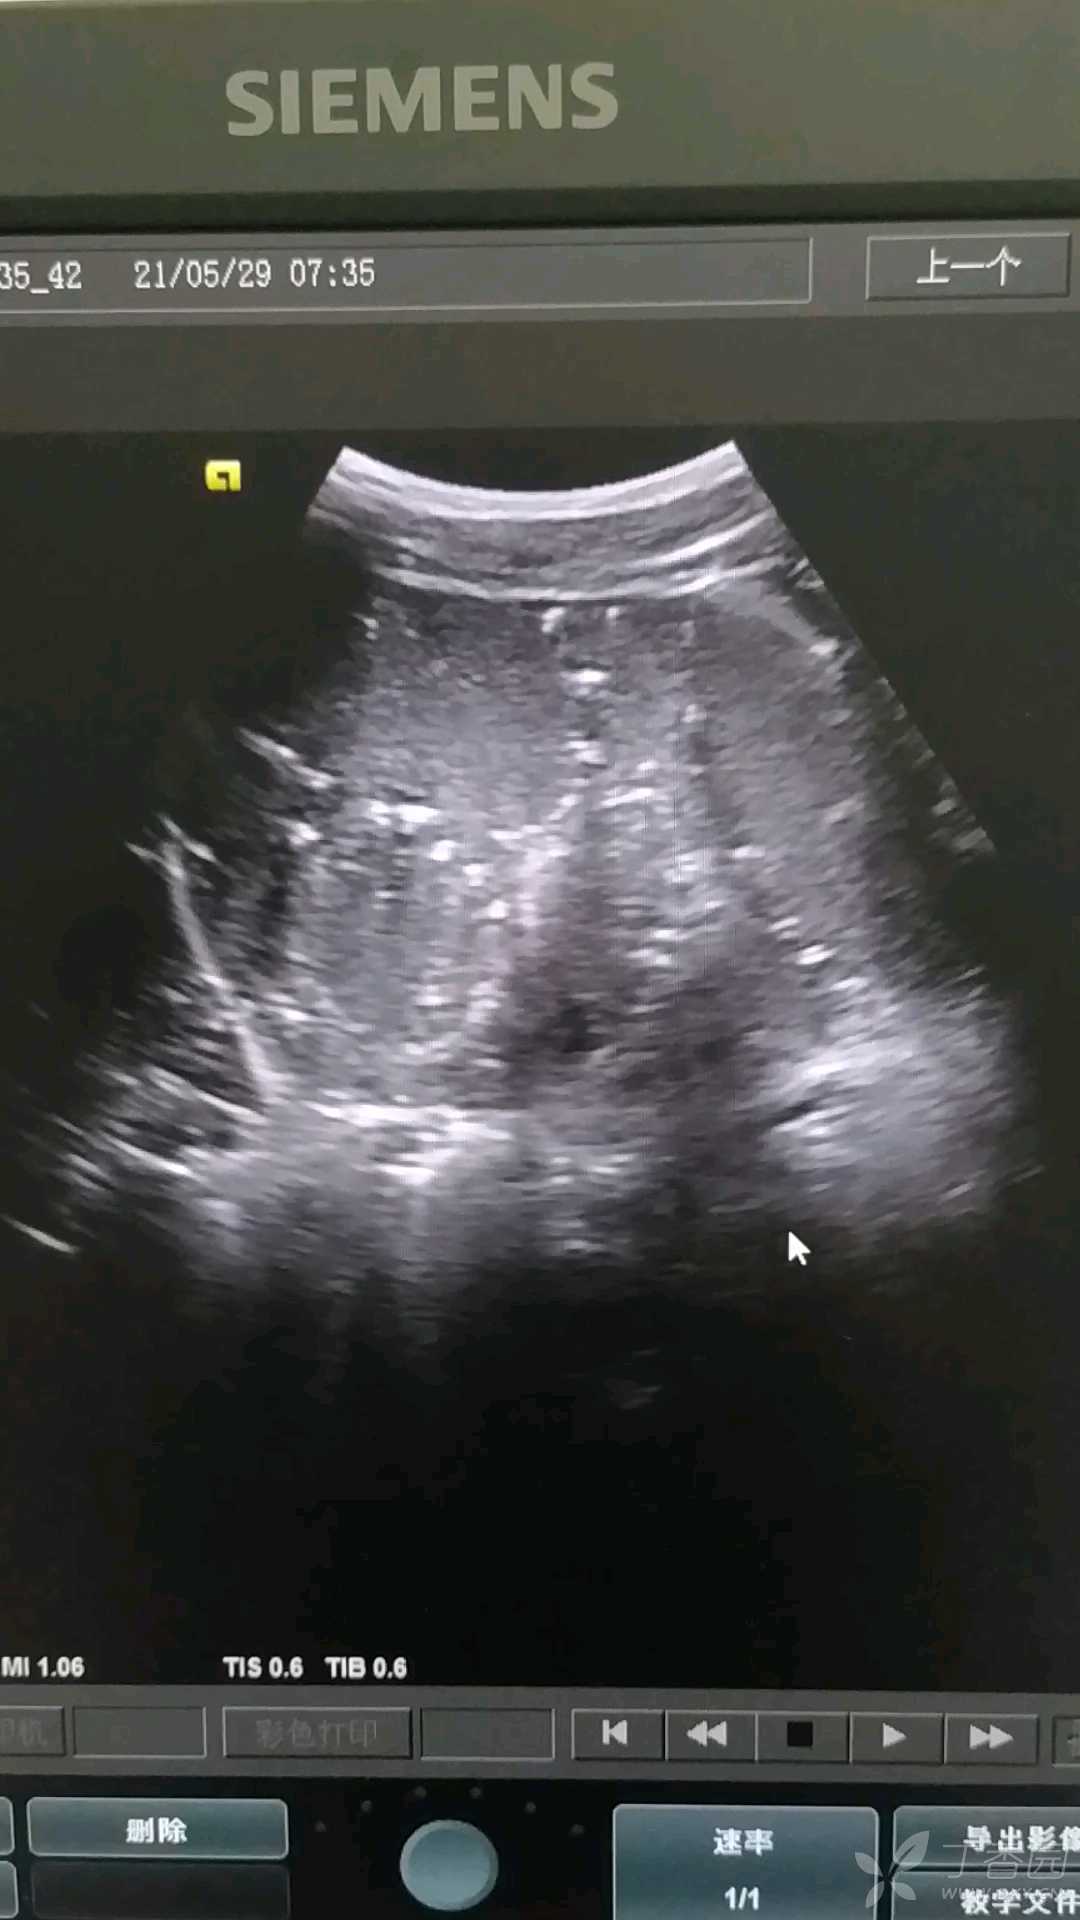

男,35岁,5年前患过结核性腹膜炎伴腹水,现已治愈。体检发现脾脏内可见多发点状钙化灶,呈满天星征。